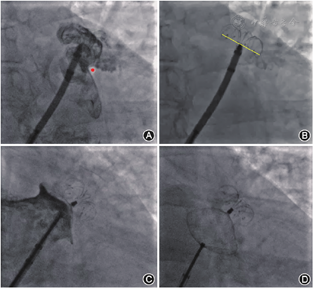

利用猪尾导管在左心耳内造影,确认猪尾导管进入左心耳,一般通过"三体位"造影图像来确认左心耳的形态:(1)RAO+头位(cranial,CRA),即右肩位,如RAO 30°~45°+CRA 20°(图2A);(2)左前斜位(left anterior oblique,LAO)+足位(caudal,CAU),如LAO 0°~15°+CAU 20°(图2B);(3)RAO+CAU,即肝位,如RAO 30°~45°+ CAU 20°(图2C)。不同患者造影角度可能会有所不同,为获得清晰的左心耳图像,可对造影角度进行调整。一般将"RAO+CAU"称为工作体位,在此体位下大多数患者左心耳能够充分展开,也可通过MSCT提前确定工作体位,在工作体位进行封堵器的展开,完成LAAO。

将猪尾导管置于左心耳的远端,尾端连接20 ml注射器;外鞘头端置于左心耳口部,尾端连接造影装置(如冠状动脉造影三联三通连接管、环柄注射器)。造影前确定X线透视工作模式以及视野大小(冠状动脉模式、帧率15幅/s为宜)。在鞘管以及猪尾导管中预充造影剂后再同时造影,可获得更清晰的左心耳影像。造影后,测量各个体位下的左心耳口部直径和可用深度,选择合适型号的封堵器,不同类型封堵器选择方式详见后述。